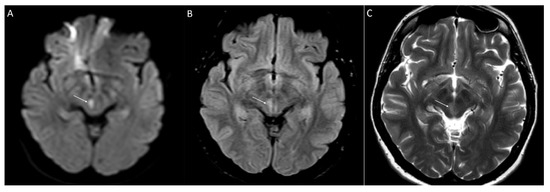

3.2. Variants of Unknown Significance and Likely Benign Variants

3.3. Newly Identified Variant